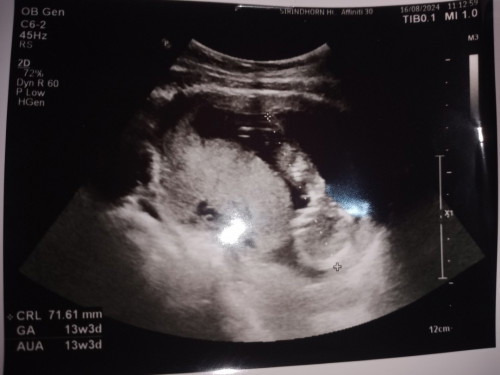

คือส่วนไหนของน้องคะ😅

แม่ดูไม่ออกเลยคะ แวะแรกเห็นเป็นขาเพราะหมอวัดความยาว มองไปมองมาเห็นเป็นส่วนหัว🤣🤣

หน้าจะส่วนลำตัวน้องค่ะช่างท้อง